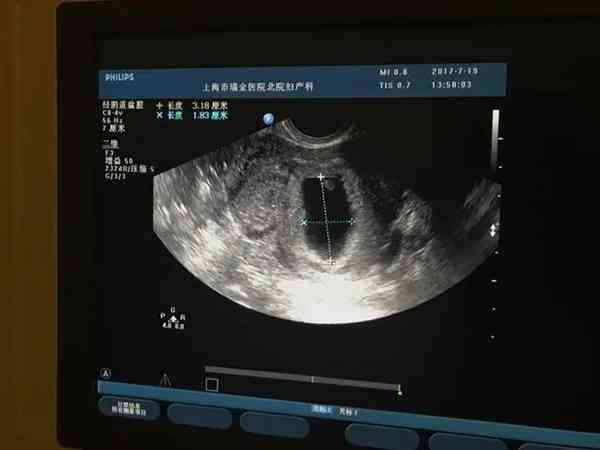

一般情况下,妊娠期30-40天才就会形成孕囊,而在孕9周有胎心胎芽在长但孕囊不长这是不正常的,有可能是胎儿发育异常的症状,甚至过一段时间胎心胎芽就会消失。而造成胎儿发育异常的主要原因可能与染色体异常、环境等因素有关,因此,如果发现此类情况是需要进行严格检查的,在医生的指导下来治疗。

正常情况下,孕囊和胎心胎芽生长是相辅相成的,如果胎芽长胎囊不长的话,绝大多数是不正常的怀孕现象,有可能在怀孕的两个月左右就会出现胚胎停止发育的。而导致胎心孕囊不同步生长的的原因有很多,可能是由于怀孕时间较短引起的,还有可能是孕检出现误差,也有可能是孕囊发育不好导致的,下面我们来具体分析一下胎芽长孕囊不长的原因: